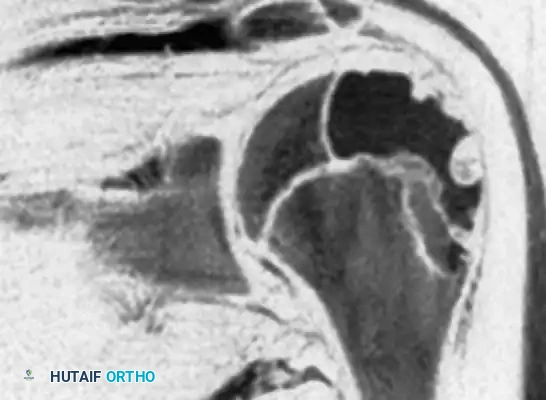

Fig. 21-4C: MRI showing the expansile nature of the lesion.

Fig. 21-4D: MRI demonstrating a distinct fluid-fluid level, indicative of a secondary aneurysmal bone cyst (ABC), which occurs in up to 20% of chondroblastomas.